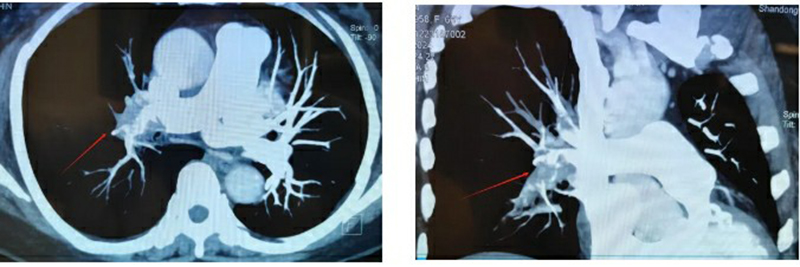

經(jīng)過初步檢查,叢樹賢副主任醫(yī)師發(fā)現(xiàn)孫大姨的情況十分危急,高度懷疑可能突發(fā)胸痛的原因與肺動脈栓塞有關(guān)。他當(dāng)機(jī)立斷,立即安排人員護(hù)送患者行肺部CTA檢查,結(jié)果令人震驚:孫大姨是雙側(cè)肺動脈及分支多發(fā)栓塞,其中右肺大面積栓塞,一旦栓子脫落,隨時(shí)有生命危險(xiǎn),十萬火急,必須馬上進(jìn)行搶救!立即啟動院內(nèi)VTE救治快速反應(yīng)機(jī)制,協(xié)調(diào)檢驗(yàn)科、放射介入科、心胸外科、護(hù)理部等多部門聯(lián)動,全力救治!

血栓救治團(tuán)隊(duì)首席專家、放射介入科劉綿春主任醫(yī)師第一時(shí)間趕來,經(jīng)過緊急討論和評估,決定立即急癥手術(shù),征得病人和家屬同意后,一場爭分奪秒的戰(zhàn)斗開始了。建立血管通路、導(dǎo)管置入、血管造影、濾器置入,再次穿刺、造影、溶栓……醫(yī)護(hù)人員動作嫻熟、操作規(guī)范、一氣呵成,成功為患者實(shí)施了下肢靜脈造影+下腔靜脈濾器置入+肺動脈造影、溶栓術(shù),造影結(jié)果顯示血栓負(fù)影明顯減少,溶栓治療取得了顯著效果。